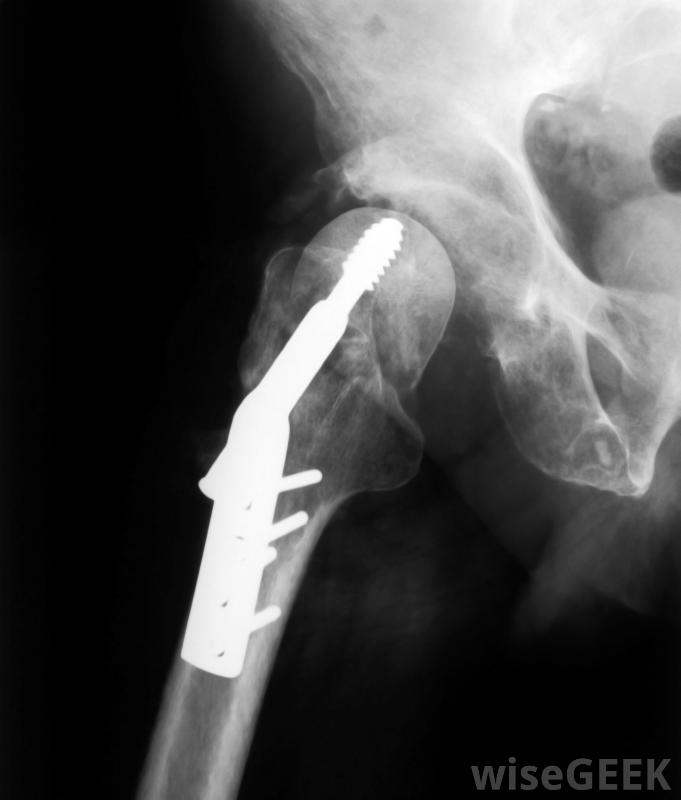

20世纪60年代,无血手术最初被定义为不使用输血。然而,这个简单的定义并没有被接受为对无血手术的完整描述,这就是为什么一些个人和组织在最初的定义基础上进行了扩展。对无血手术的更彻底的定义包括完全避免输血或血液制品的要求。重点在于避免输血和避免使用血液制品。可以使用高度先进的外科手术程序和技术来消除使用输血或血液制品的需要髋关节修复和置换手术通常不需要输血首先包括单纯的愿望和企图排除使用输血,第二个绝对需要这样的排除。这就是为什么并非所有的无血手术都是真正的无血的。这一说法是指在手术或其他医疗程序中避免使用输血或血液制品的可能失败的尝试。医疗程序和实际的手术都可以是无血的,因此可以这样说尽管有许多预防措施来预防问题,但大多数人还是宁愿避免输血人们避免输血或使用血液制品是有充分理由的。各种形式的肝炎和人类免疫缺陷病毒(HIV)等疾病可能是通过使用输血或血液制品而感染的有助于防止这种传播,并不能保证病人不会接受受污染的血液。持宗教观点反对献血和接受血液的人也属于对无血手术和医疗程序感兴趣的人可以进行的无输血手术包括髋关节和膝关节置换术和心脏直视手术。有时也可以选择使用通常被认为是安全的血液和血液制品的替代品,如生理盐水和乳酸林格他们接受无血手术,即所谓的"无血医学指令"。他们也可以通过另一个称为"预先医疗指令"的法律文件来告知他们拒绝使用血液或血液制品。这样的文件是关于医疗护理的指示,法律要求医疗保健提供者尊重并遵守这一原则。

心脏直视手术是一种无需输血即可完成的手术。